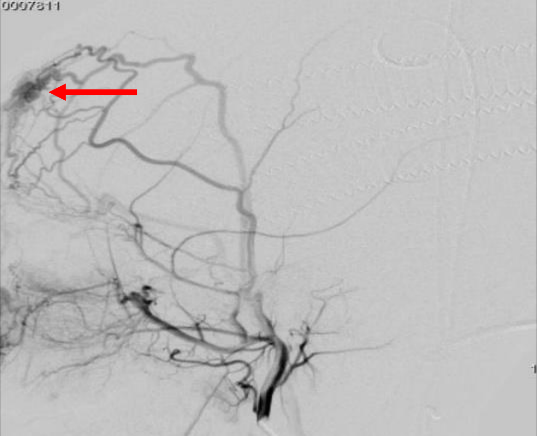

图2 患儿临床资料 A.超声引导下经皮穿刺瘤巢造影 B.术后造影显示瘤巢内畸形血管团基本消失(红色箭头指示)

完善相关术前检查后,手术历时2小时顺利完成,按小儿普外手术团队术前备选方案,超声准确定位穿刺点,超声透视引导下经皮穿刺到达瘤巢,造影证实为瘤巢位置后(图2A),在超声实时监视下注入无水乙醇,将瘤巢栓塞(图2B)破坏。术中未置入弹簧圈,避免金属异物永久存留,最大限度的节约患者医疗费用。手术创面仅有两个针眼,将病人创伤降到最低,术中出血仅2ml。术后再次造影发现瘤巢明显缩小,术后患儿无特殊不适,术后左额部包块明显缩小,包块波动消失(图2B)。